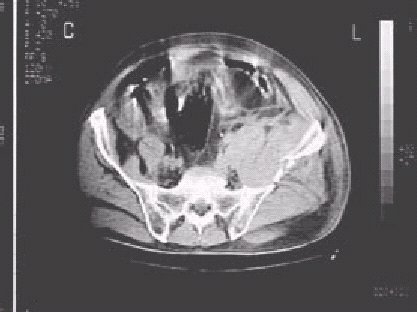

Figura 9 .—Imágenes de tomografía computerizada en un paciente con hematoma retroperitoneal en relación con fragmentos óseos de una fractura de pelvis.